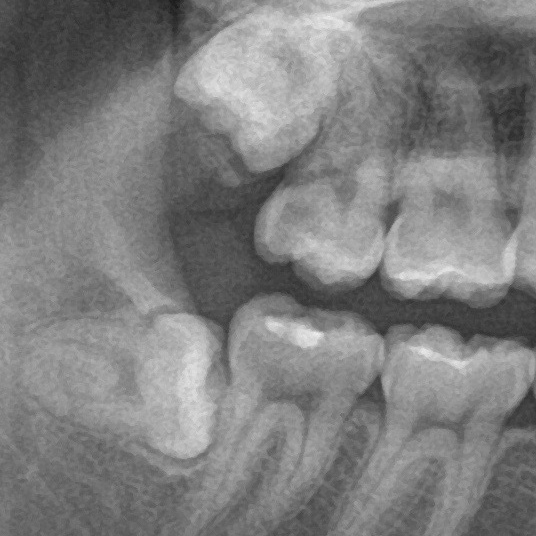

抜かないで良い場合

親知らずがまっすぐ生えていて、なおかつ反対側の親知らずとしっかり噛んでいて、むし歯や親知らず周囲の炎症を起こしていない場合は抜く必要はありません。

しかし、現代人の顎は食事の変化に伴い小さくなってきており、親知らずが正常にはえて機能している人は少なく、多くの人は何らかの問題を抱えていることがほとんどです。